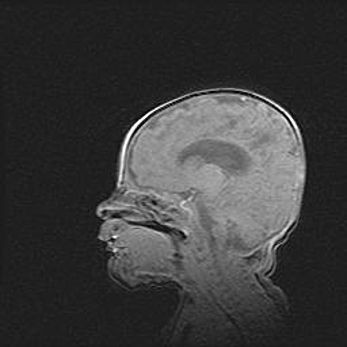

Наружная гидроцефалия с возможной атрофией височных областей.

Возраст: 28 дней

Вес: 3670 г

Пол: мужской

Окружность головы: 38 см

Срок гестации: 40 недель

Гидроцефалия головного мозга у новорожденных – это заболевание, которое характеризуется скоплением избыточного количества спинномозговой жидкости в желудочковой системе головного мозга в результате затруднения её перемещения от места выработки к месту поглощения в кровеносную систему или вследствие нарушения абсорбции. При открытой наружной форме гидроцефалии у новорожденных расширяются и переполняются субарахноидные пространства.

При нормотензивных  формах,  которые,  как  правило,  являются  следствием  перенесенных ишемических  повреждений  паренхимы  мозга,  возможно  сочетание микроцефалии  с нормотензивной гидроцефалией. В основе данных изменений лежит атрофия больших полушарий с преимущественной  локализацией  в  лобно-височных  областях.